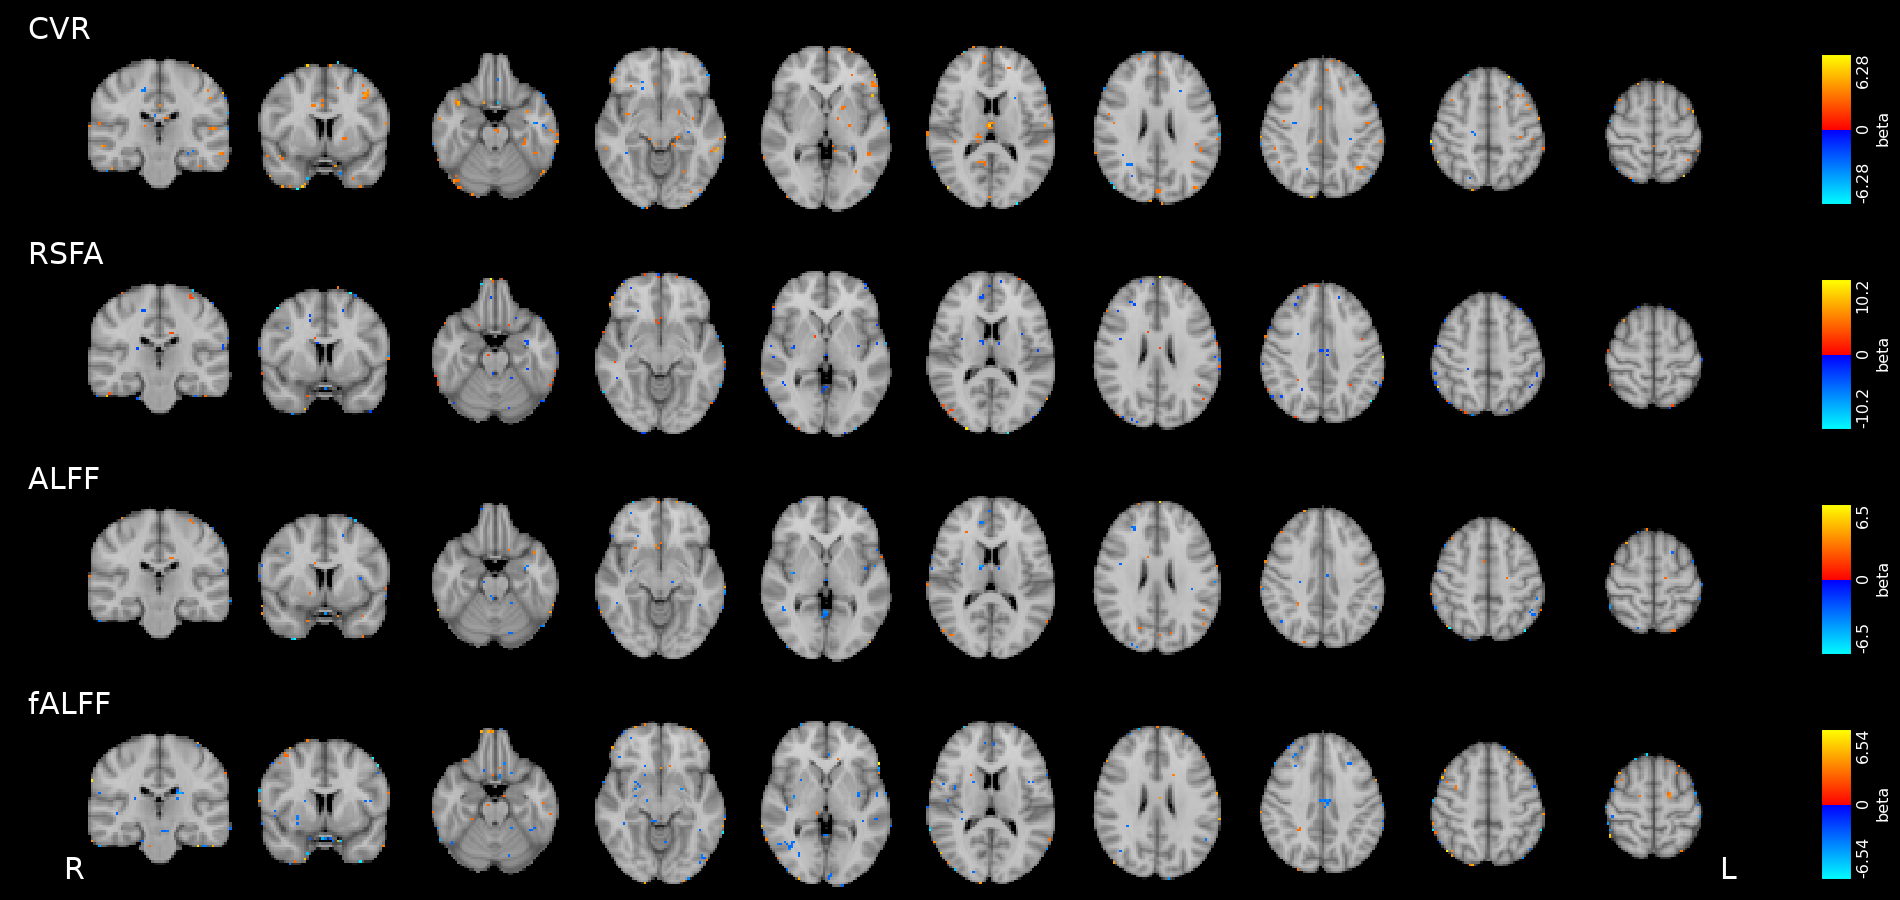

Results: blood pressure

Results: blood pressure

Results: blood pressure

Both MAP and PP should be taken into account in CVR experiments, especially in comparisons between subjects or between regions!

Results: sex

- Females show higher CVR than males in most of the GM

- Previous studies report CVR higher in females¹, in males², or no differences between the two³

- A possible cause of this difference might be related to hormonal changes during the menstrual cycle

1. Kastrup et al. 1997, 1998 (Stroke), Tallon et al. 2020 (Exp. Psychol.); 2. Kassner et al. 2010 (J. Magn. Reson. Imaging)

3. Chen et al. 2021 (Int. J. Imaging Syst. Technol.), Jiménez Caballero et al. 2006 (Rev Neurol)

Results: sex

Increased blood pressure

results in localised increases in CVR.

The sex of the participant can affect CVR too.

Take home message #2

- Stationary blood pressure changes, expressed as MAP and PP, as well as sex, impact regional CVR estimation differently across sessions and subjects

-

Dynamic blood pressure changes are expected to impact CVR estimation, hence continuous blood pressure recordings are required to assess the matter

- Future studies should expand the impact of sex on CVR estimation by assessing the impact of more defined factors (e.g. hormonal fluctuations)

-

Dynamic blood pressure changes are expected to impact CVR estimation, hence continuous blood pressure recordings are required to assess the matter